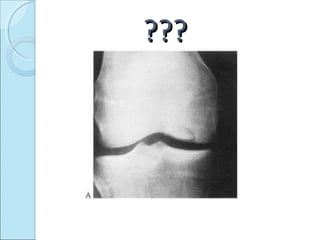

PLAIN RADIOGRAPHS

 May be normal.

 When visible

=radiolucent ring surrounding bony fragment.

=in profile-loose body opposite to pit in bone.

Loss of sharp cortical line of articular surface.

X-ray knee frontal view---radiolucent line on lateral aspect

of medial condyle extending up to articular surface. Joint

space normal.